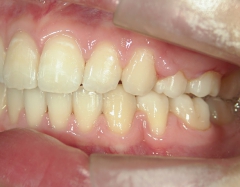

矯正歯科(全顎ワイヤー矯正)治療後

矯正歯科 治療後